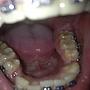

[問題] 牙肉有可能被矯正器戳到化膿嗎?消失

[ teeth_salon ]6 留言, 推噓總分: +2

作者: vriechvras - 發表於 2016/05/31 19:32(10年前)

1Fvriechvras: 難怪會化膿 剛把軟蠟拿下來發現 那邊的肉被戳到流血QQ05/31 20:07